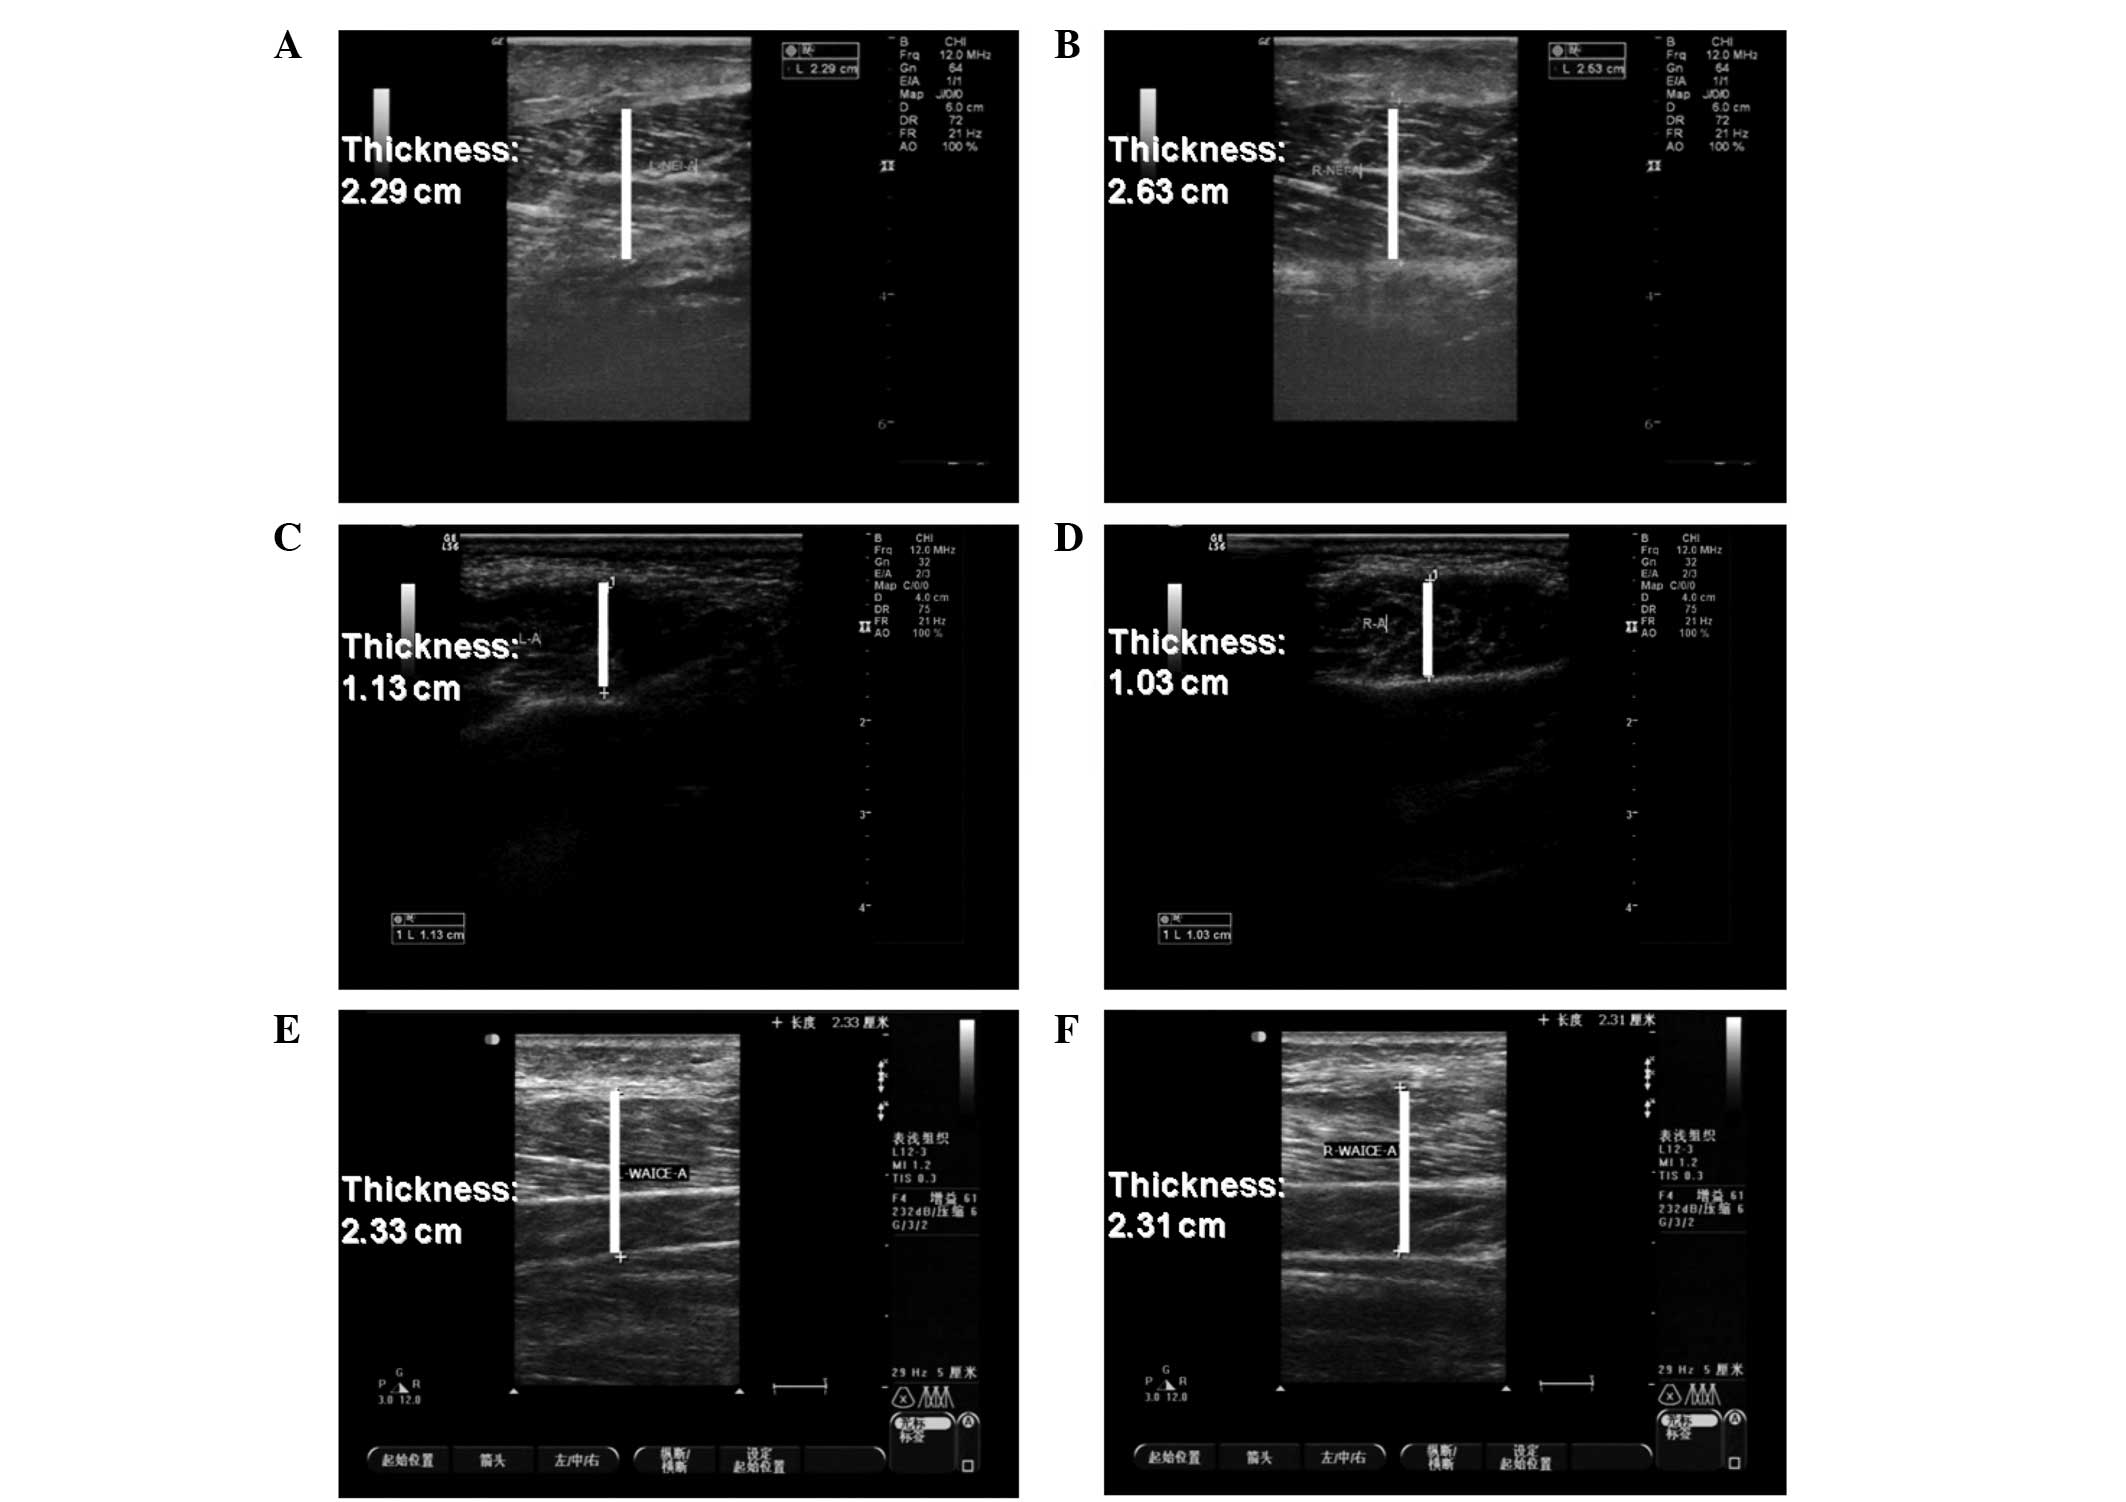

The mean masseteric thicknesses prior to injection with botulinum toxin A were 2.79 cm on the left side and 2.78 cm on the right side, as measured by ultrasound. The mean masseteric thicknesses at 6 and 12 months after injection were 1.43 and 1.31 cm on the left side, and 2.24 and 2.45 cm on the right side, respectively (Figs. 1, 2 and 3A). The mean masseteric thicknesses prior to treatment with RF ablation were 2.93 cm on the left side and 2.73 cm on the right side. The mean masseteric thicknesses at 6 and 12 months following surgery were 1.23 and 1.11 mm on the left side, and 1.02 and 1.05 cm on the right side, respectively (Figs. 3B, 4 and 5). In the botulinum toxin A injection group, the masseteric thickness measured by ultrasound decreased to the lowest point 6 months after the injections, but increased 12 months following the injection. However, in the RF ablation treatment group, masseteric thickness decreased steadily over the 12 months following surgery (Figs. 2, 4 and 5).

Figure 2

Ultrasound evaluation of the right and left sides of the patient shown in Fig. 2 (A and B) prior to treatment, (C and D) 6 months after treatment and (E and F) 12 months after treatment. The white bar indicates the thickness of the masseter muscle.

Ultrasound evaluation of the right and left sides of the patient shown in Fig. 1 (A and B) prior to treatment, (C and D) 6 months following treatment and (E and F) 12 months after treatment. The white bar indicates the thickness of the masseter muscle.